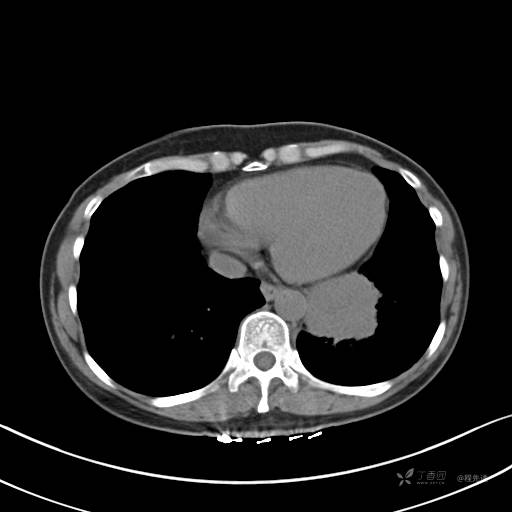

增强静脉期

静脉期CT值约84HU